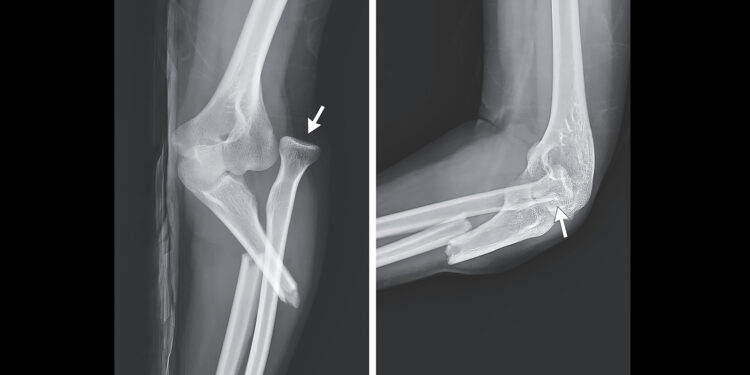

(MedPage Today) — The weather outside might be frightful — but so is a radiograph of the arm one woman broke while ice skating.

The 26-year-old arrived at the emergency department at Far Eastern Memorial Hospital in Taipei City, Taiwan, with…